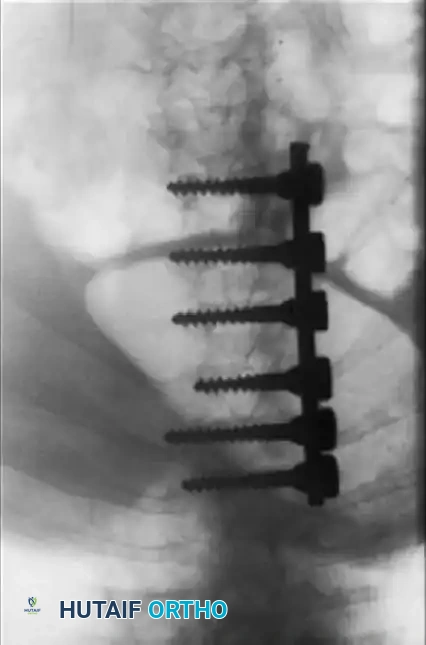

Fig. 38-219 B & C, Postoperative anteroposterior and lateral radiographs demonstrating successful spinal arthrodesis with pedicle screw instrumentation, restoring sagittal balance without neurological compromise.

Additional imaging demonstrating the complex osseous anatomy and pedicle morphology that must be navigated during instrumentation in skeletal dysplasias.